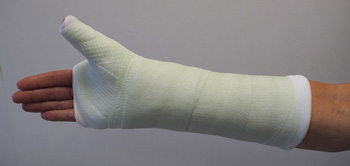

For this type of fracture, your doctor may place your forearm and hand in a cast or a splint. The cast or splint will usually be below the elbow and include your thumb.

If your doctor treats this type of fracture with a cast, the cast may include the thumb and extend above the elbow to help stabilize the fracture

For some fractures, a cast that covers the forearm, wrist, and thumb may be used to help keep the bone fragments in place while they heal.